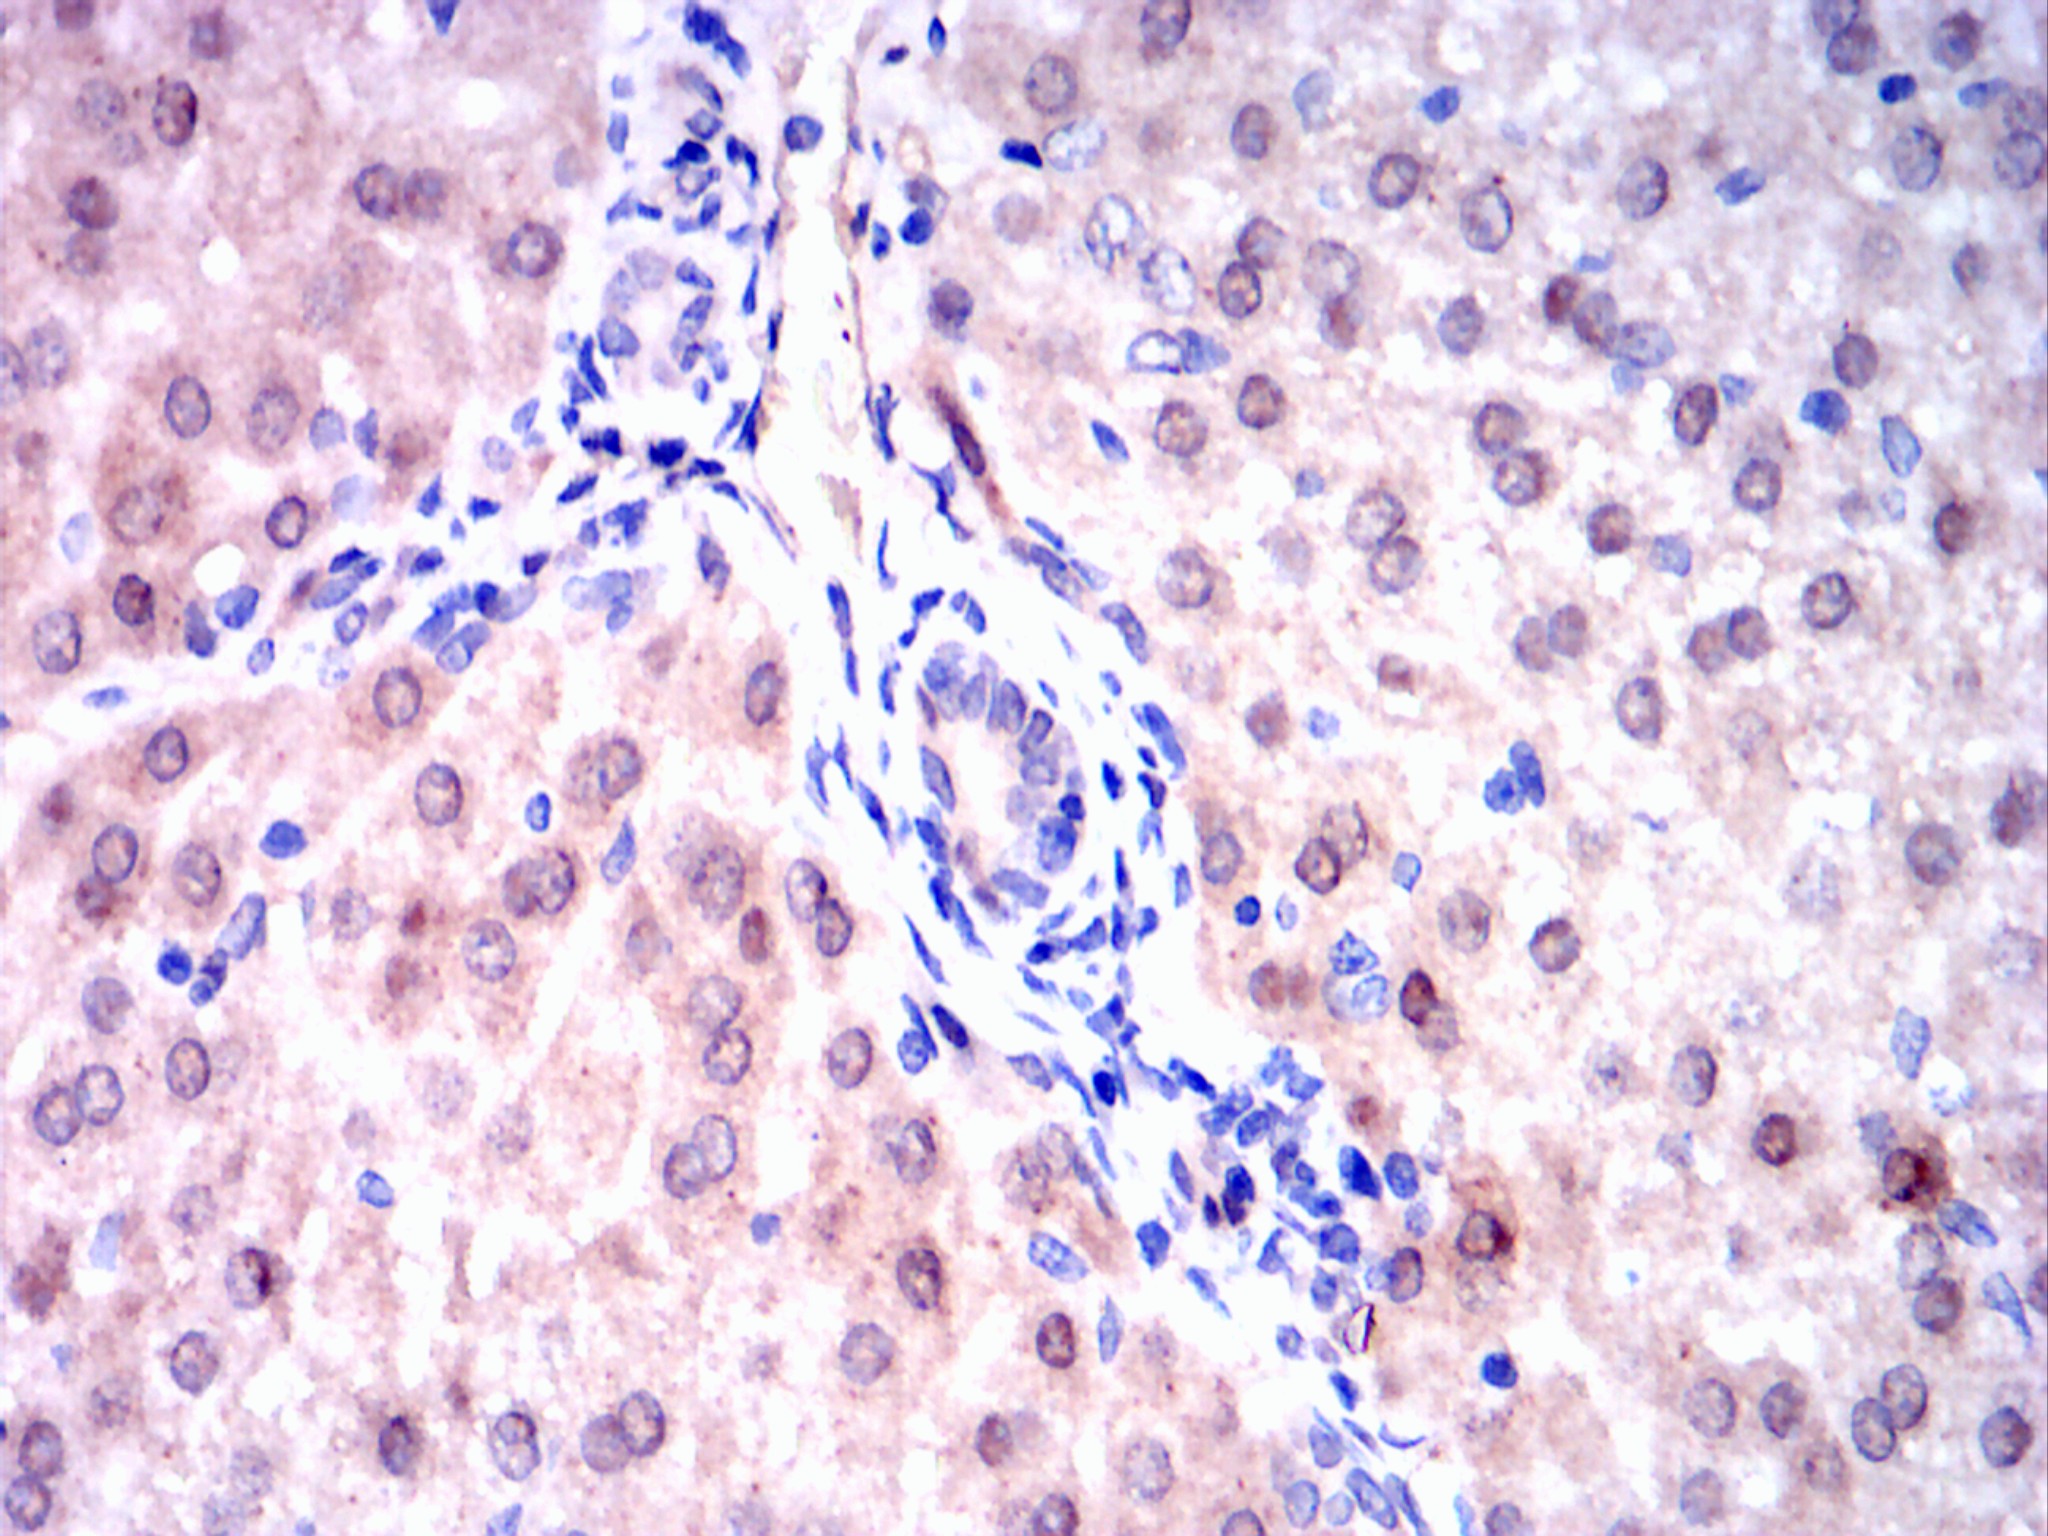

Immunohistochemical analysis of paraffin-embedded rabbit liver tissues using Visfatin(PBEF) mouse mAb with DAB staining.